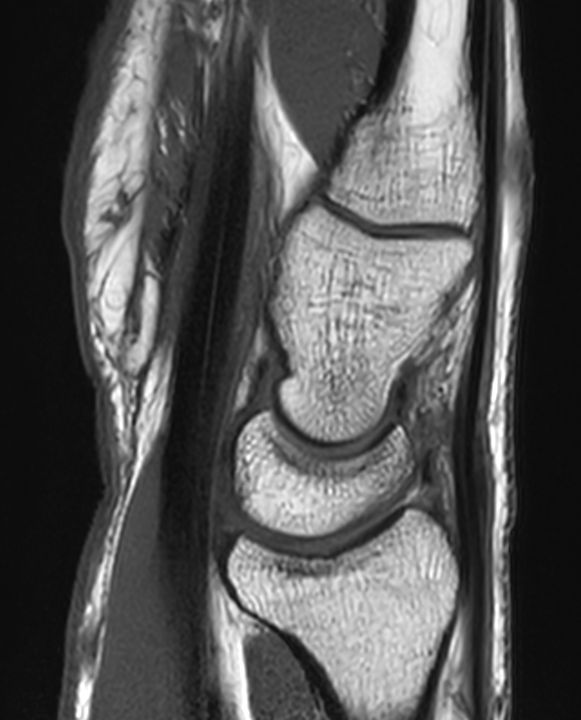

Sagittal T1w TSE

Sagittal T1w TSESmartSpeed

Sagittal T1w TSESmartSpeed Resolution